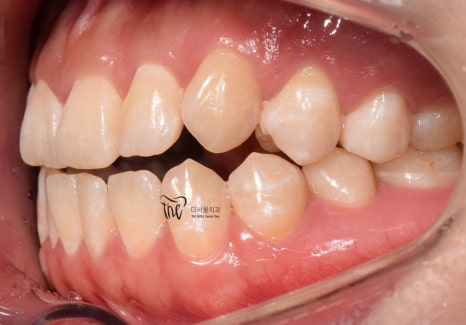

구강 내 사진을 보면, 전형적인 Open bite 의

형태를 띄고 있는 것을 보실 수 있습니다.

그 정도는, 그렇게 심하지는 않으나

치아교정 을 받지 않는다면 턱관절 에

더 큰 문제를 일으킨다는 것을 본인 스스로도

잘 알고 있었기 때문에 저에게 진료를

의뢰했었습니다.

이제 윗니가 아랫니를 겹치게 덮는 모양이

나오게 되면서 치료를 끝마치게 되었네요.